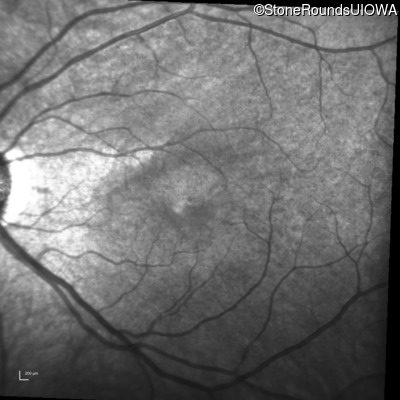

Infrared Fundus Photograph - Right - 20/40 +1

Exemplar